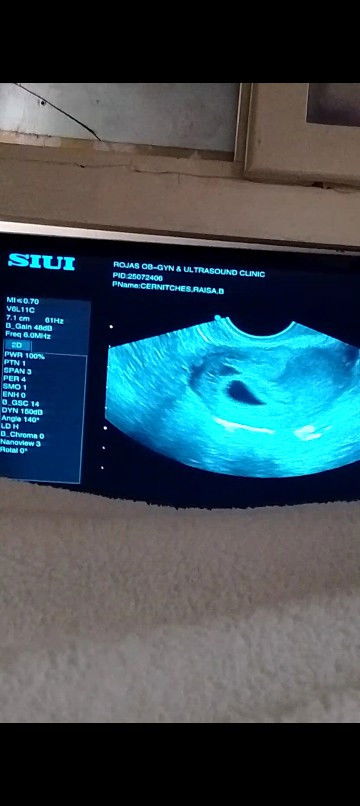

eto po result Ng trans v ko

Mi wait ka lang ng 2 weeks balik ka ulit pahinga mas okay if mag bedrest ka para mas madevelop si baby. Wag ka pakastress masyado pa yan maaga kasi nag base lang naman sila sa first day ng mens mo pero di naman sure na yun talaga nabuo eh. Maaga lang siguro na detect ng PT.